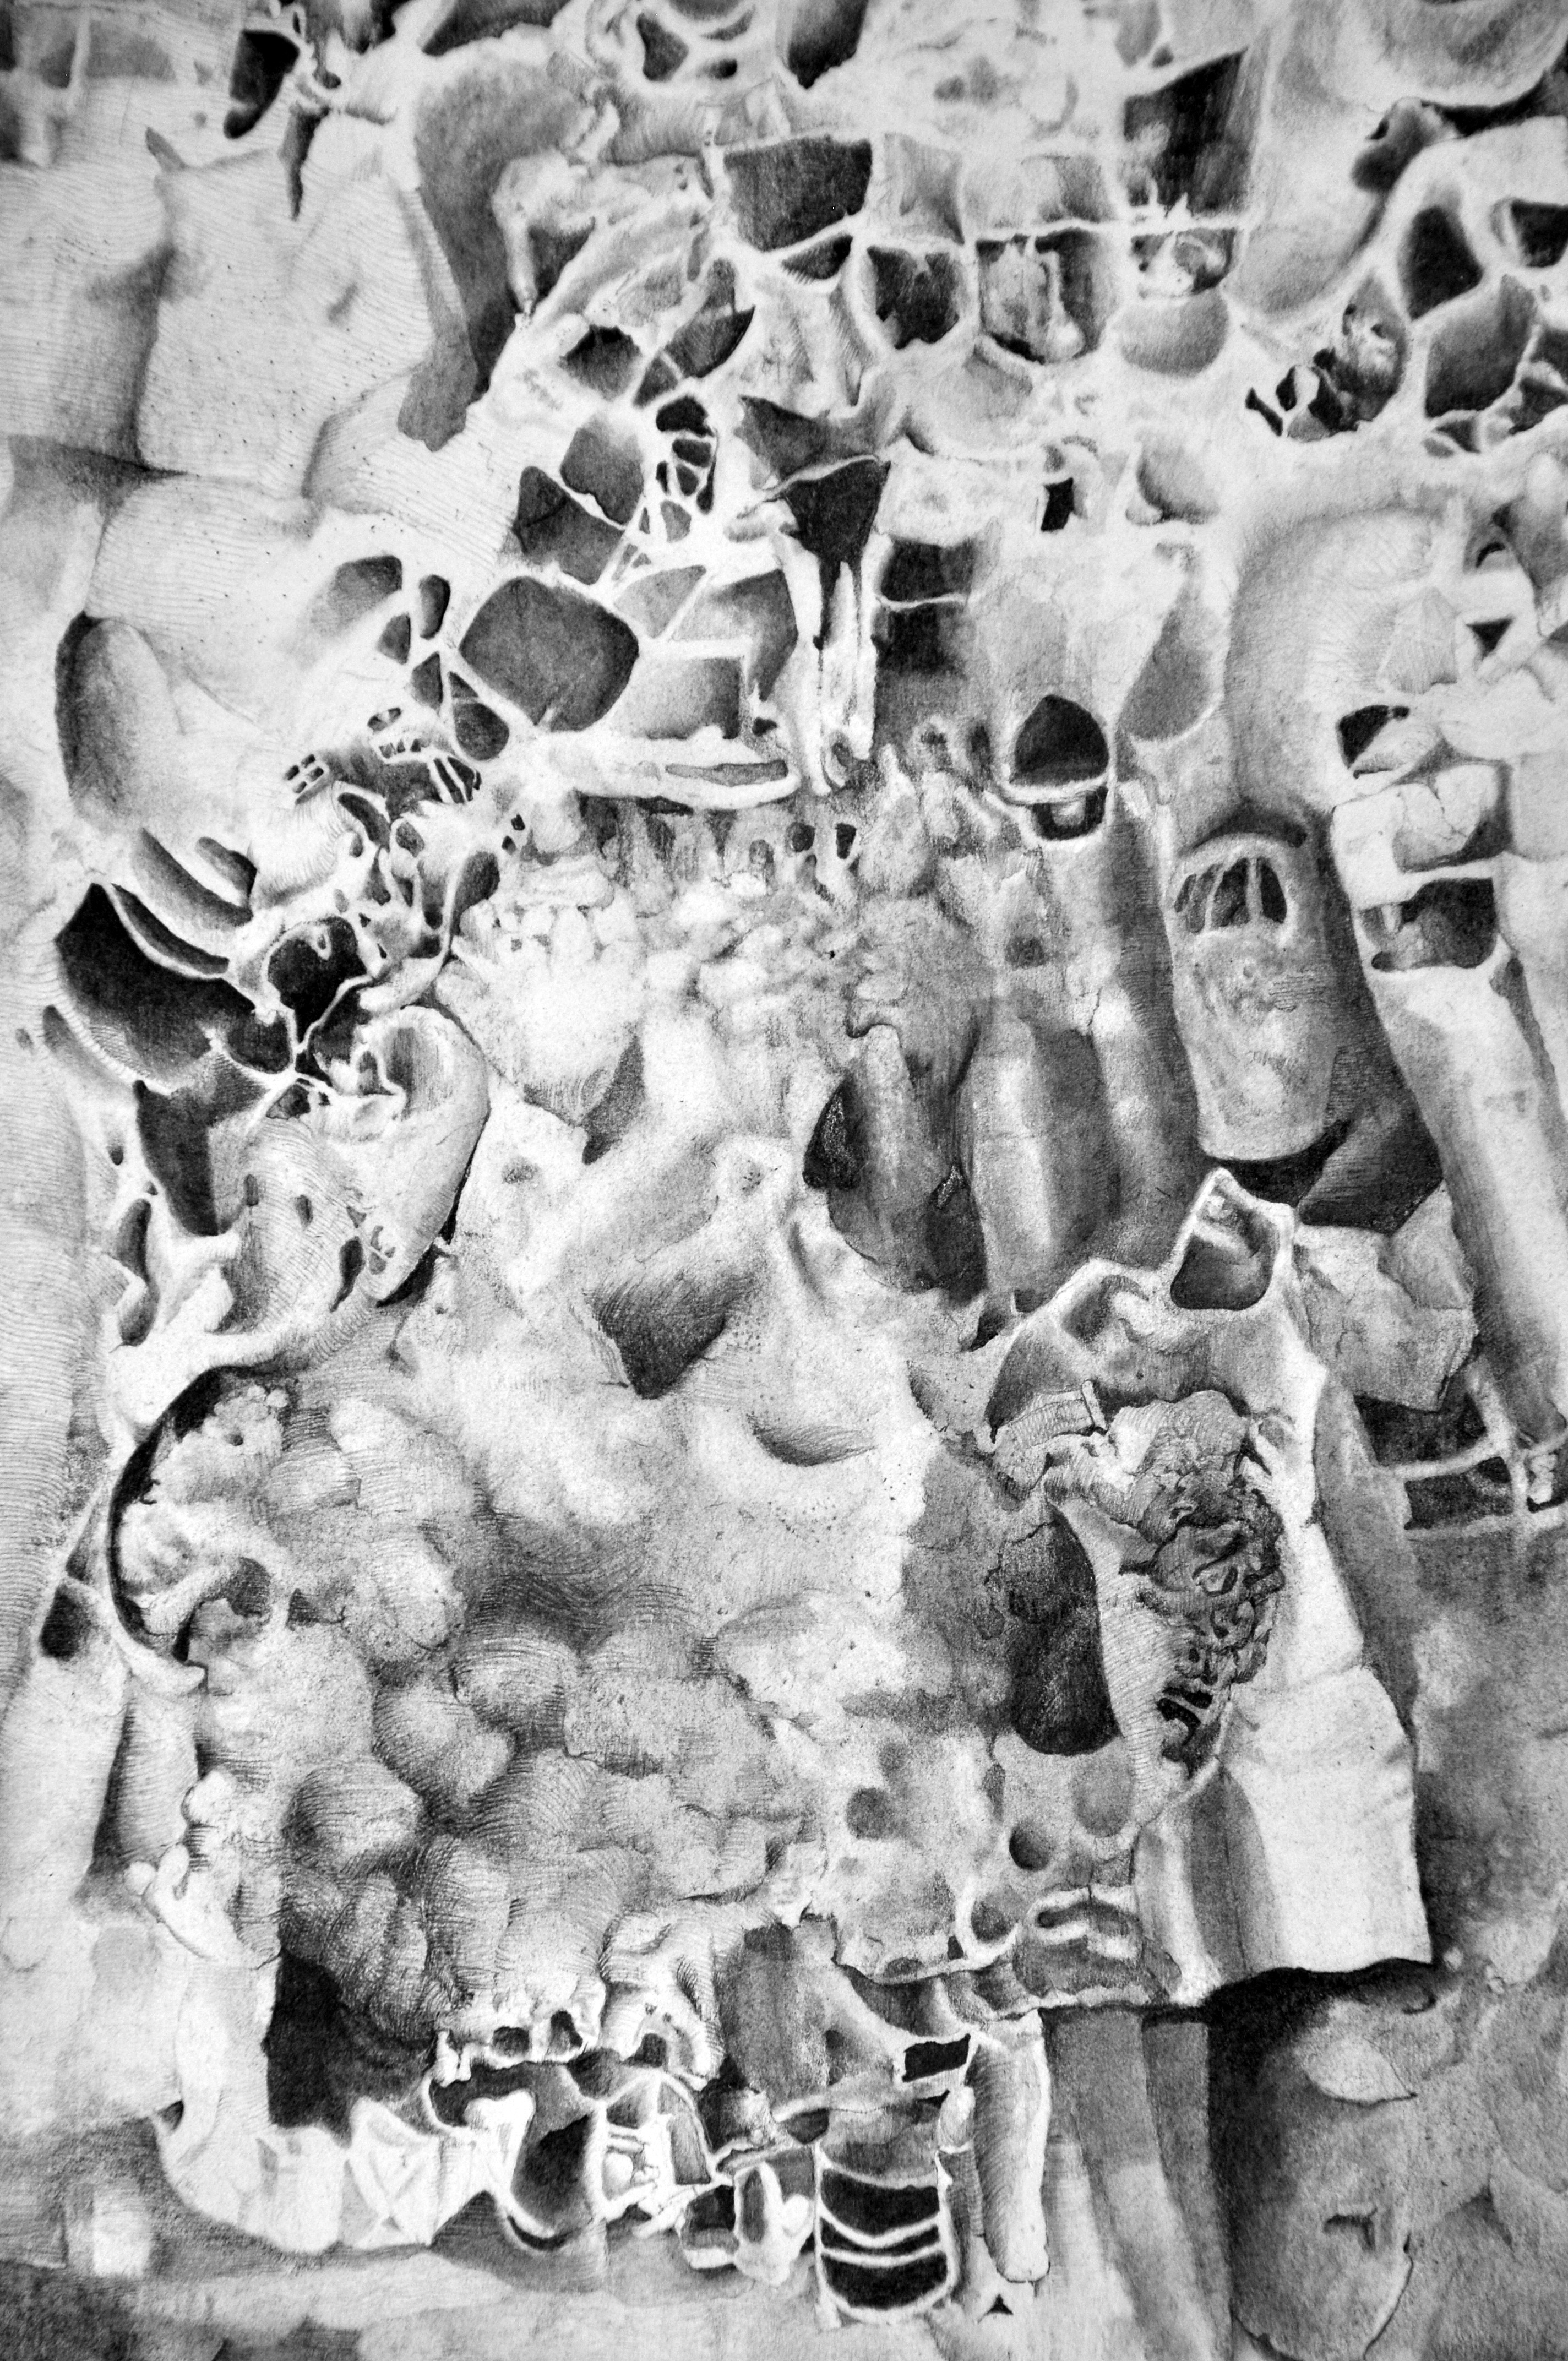

Visualizing Melanoma

Charcoal and graphite on paper with ink on Plexiglas and aluminum mounts

From Visual Pathology: a collaboration with Galveston Art Center and the Department of Pathology at the University of Texas Medical Branch (UTMB).